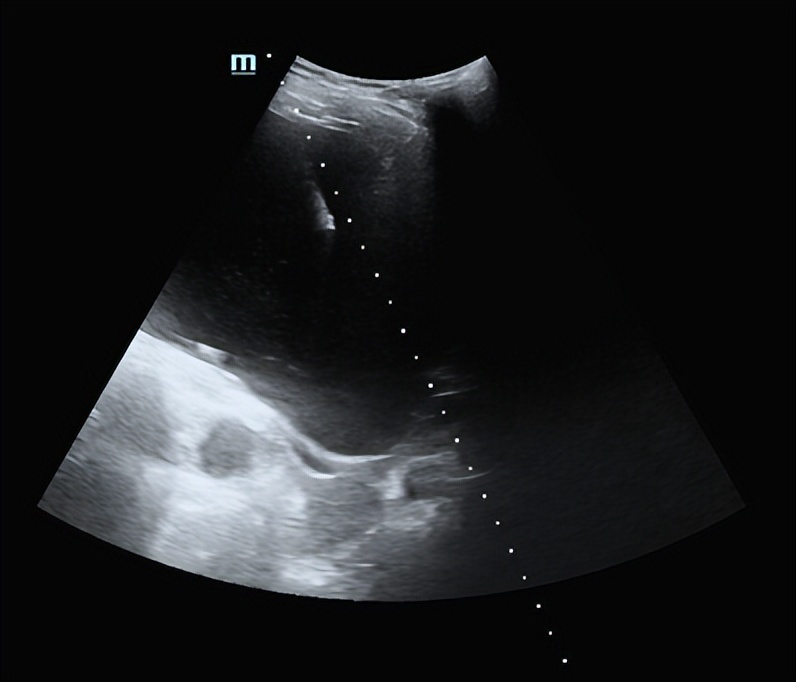

重叠囊肿连环穿刺

按照大小排序,对第2、3号囊肿进行常规穿刺硬化治疗,采用18G PTC针穿刺,抽吸出囊液95ml、75ml,生理盐水冲洗囊腔,40ml、30ml无水乙醇硬化囊腔10分钟抽出,囊腔内保留无水乙醇3ml。